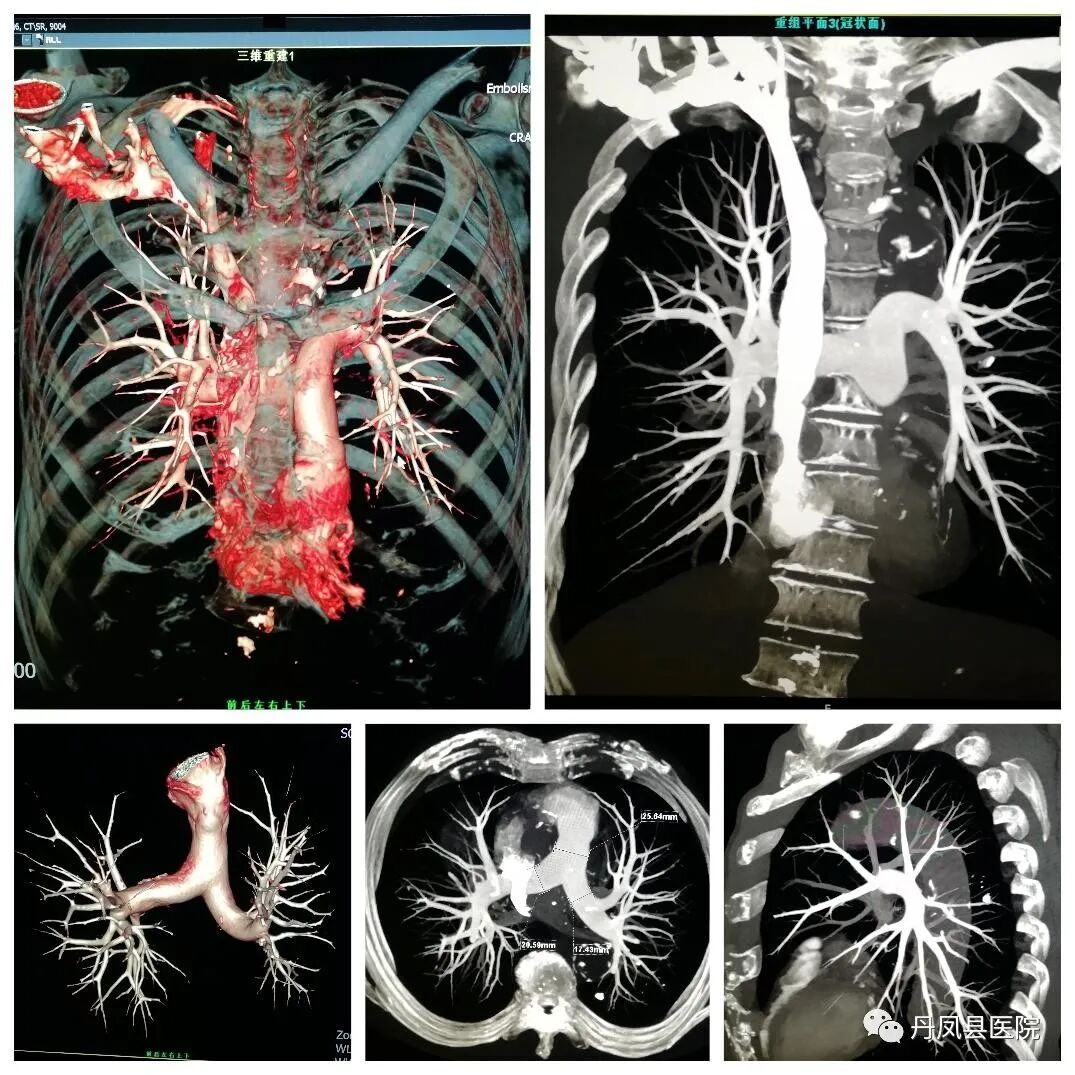

CTCT室目前开展全身各部位常规CT平扫、增强CT扫描、CT血管造影(CTA)、冠状动脉CTA、CT尿路造影(CTU)及骨关节CT三维重建等检查技术。64排128层CT具有扫描速度快、分辨率高、定位准确、低剂量辐射等优势,同时运用强大的后处理工作站进行数据处理、多平面重建,利用PACS网络传输系统与医院HIS系统对接,实时将检查图像、影像诊断结果传输到临床医生工作站终端,满足临床医生和患者的需求。尤其是CT血管造影、冠状动脉CTA检查技术应用的日益成熟,解决了患者三级医院看病难的实际问题,也填补了我县在这方面的空白。

肺动脉CTPA

肺动脉CTPA诊断肺栓塞的敏感性可达75%~100%,特异性可达80%~100%,对于叶、段动脉显示准确性更高,有助于明确肺动脉内栓子的位置、范围、程度及肺动脉血流动力学状态等。